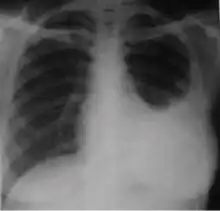

5. Hilar or mediastinal lymphadenopathy (bihilar lymphadenopathy) - Enlargement of lymph nodes in one or both hila or within the mediastinum, with or without associated atelectasis or consolidation.

-

Chest x-ray showing bilateral hilar adenopathy of primary pulmonary TB